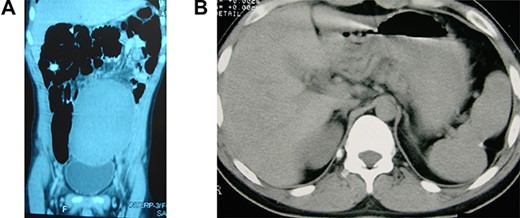

A 14-year-old boy was referred to our hospital due to a long-term history of lower abdominal pain associated with dysuria, tenesmus and constipation associated with a visible tender pelvic mass. He also exhibited a retarded growth (152 cm in height) and sexual underdevelopment characterized by lack of sexual maturity and absence of secondary sexual physical appearance with no facial, pubic and axillary hair growth. Laboratory exams indicated a reduced platelet count of 114 × 103/μl, a white blood cell count of 6.2 × 103/μl and a hemoglobin level of 11.2 g/dl. An axial CT showed the absence of the spleen in the left subphrenic space and an enlarged spleen, measuring 22 × 16 × 13 cm, within the pelvic region (Fig. 1A).

Wandering and twisted splenomegaly. (A) CT scan of the abdomen showing a displaced ectopic spleen in the left flank and pelvic region, characteristic of a wandering spleen. Observe the absence of the spleen in the left hypochondrium. (B) The spleen after detorsion and splenopexy in the left hypochondrium. Observe the reduction of the spleen to a normal size four years after the splenopexy.